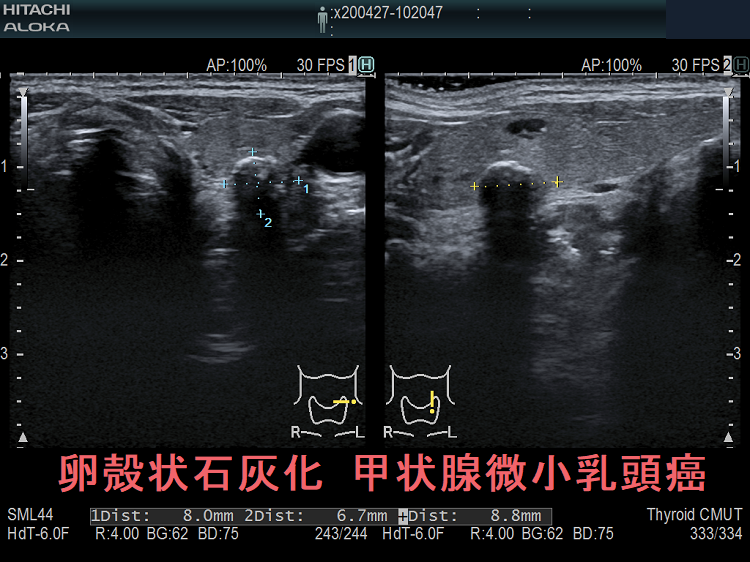

- 1cm以上の甲状腺乳頭癌と甲状腺微小乳頭癌で、石灰化率に有意差はないとされます[Exp Ther Med. 2014 Oct;8(4):1335-1339.]。しかし、甲状腺微小乳頭癌の石灰化パターンは、1cm以上の甲状腺乳頭癌とやや異なります。微細石灰化・斑点状石灰化・卵殻状石灰化の頻度は1cm以上の甲状腺乳頭癌と同じですが、甲状腺微小乳頭癌では破片状・塊状石灰化の頻度が多い。

被膜石灰化(卵殻状石灰化)は、甲状腺微小乳頭癌に特異的ではなく、腺腫様結節、甲状腺濾胞癌でも認めます。